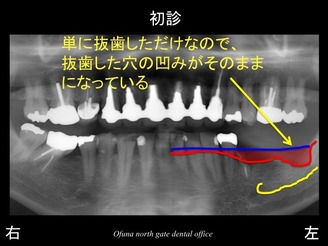

以下が初診時です。

下顎の左側の歯が抜けてしまって噛めないとのことで来院されました。

下顎左側の奥歯が2歯分欠損していました。

いつものように 骨吸収の状態を分かりやすくするために

骨吸収の状態を線で書いたのが以下のレントゲンになります。

さらに分かりやすくするために 骨吸収部位を赤色の領域で表します。

特に一番奥では、骨吸収が非常に大きいのが分かるかと思います。

通常、インプラント治療を前提として抜歯した場合には、抜歯直後に抜歯した穴ができるかぎり 早く骨で埋まるような治療法を行います。

単に抜歯しただけでは、穴は埋まりにくいのです。

抜歯した穴に骨が再生しやすい行う治療法をソケットプリザベーション法 と言います。

このソケットプリザベーション法 を行うかどうかが今後のインプラント治療に大きく影響するのです。

今回の症例では、下顎の一番奥の歯は、他歯科医院で抜歯されました。

おそらくソケットプリザベーション法 は行っていないと考えられます。